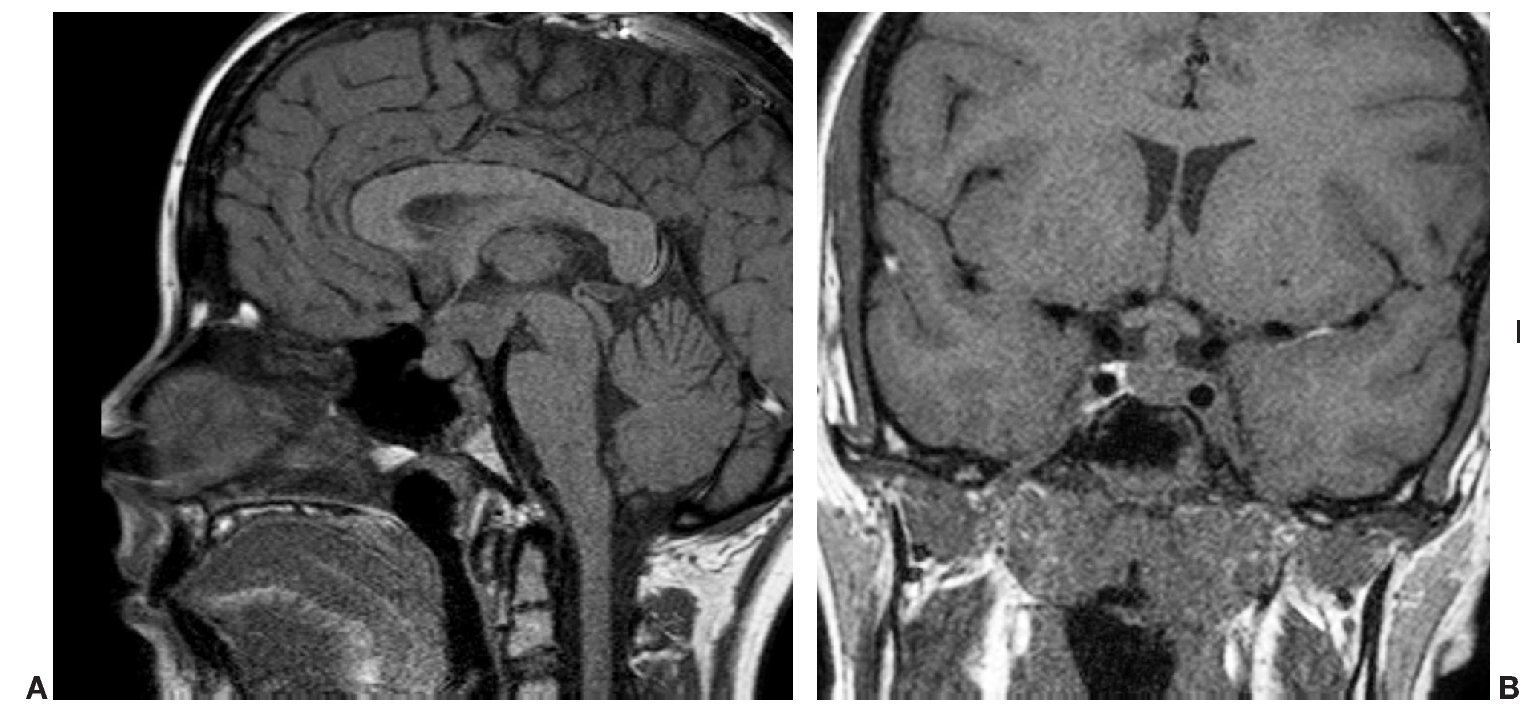

Paciente varón de 14 años de edad, con talla baja y panhipopituitarismo.

Fig. 3.

Comentario en las páginas 339-40